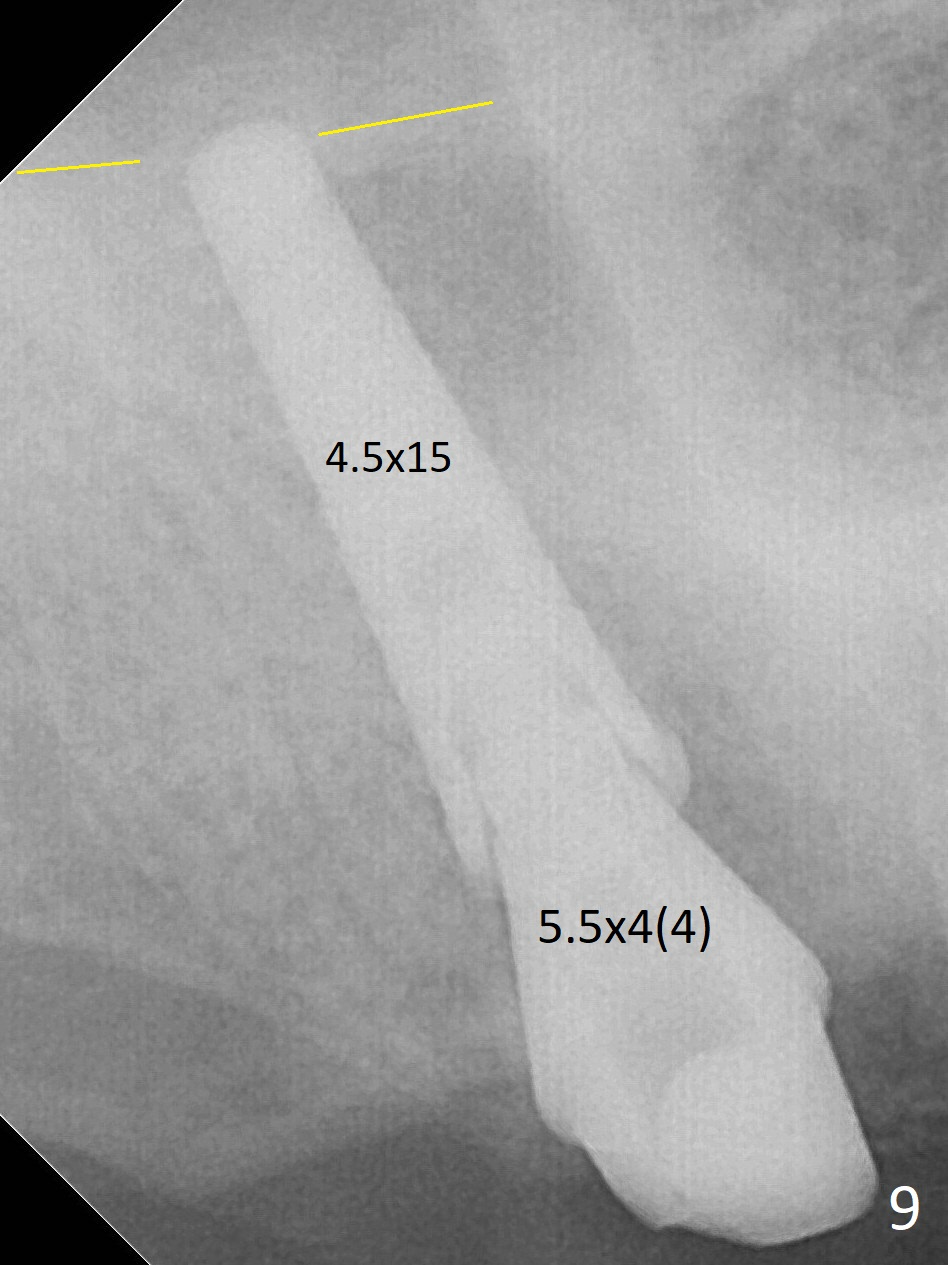

Fig.5 shows the mesial slope of the socket (M), which is more or less the center of the socket mesiodistally. If the osteotomy were set up in the red circle (Fig.6) in the mesial slope (Fig.8 green dashed line), the trajectory of 4.5x11 mm dummy implant (Fig.7) would be more ideal (Fig.8 red outline) with more native bone contact. Finally a longer IBS implant is placed (4.5x15 mm, Fig.9,10) to achieve primary stability (50 Ncm). When the provisional is removed for impression 3 months 10 days postop, the implant is found to have been placed distopalatally (Fig.13), which should have been avoided. It appears essential to use guide for a distal implant. It is agonizing to re-encounter the off-axial implant (Fig.14) and the distopalatal access hole (Fig.15) 1 year post cementation. It is also amazing that the abutment screw has not loosened. A fair-sized piece of bone graft has just been removed buccally (Fig.15,16). The patient complains of sensitivity 2 years 3 months post cementation, although there is no abnormality around the implant crown. Guided surgery is essential to avoid restoration complication. There is no thread exposure nearly 3 years post cementation; in fact the apical portion of the abutment is covered by the bone (Fig.17,18).